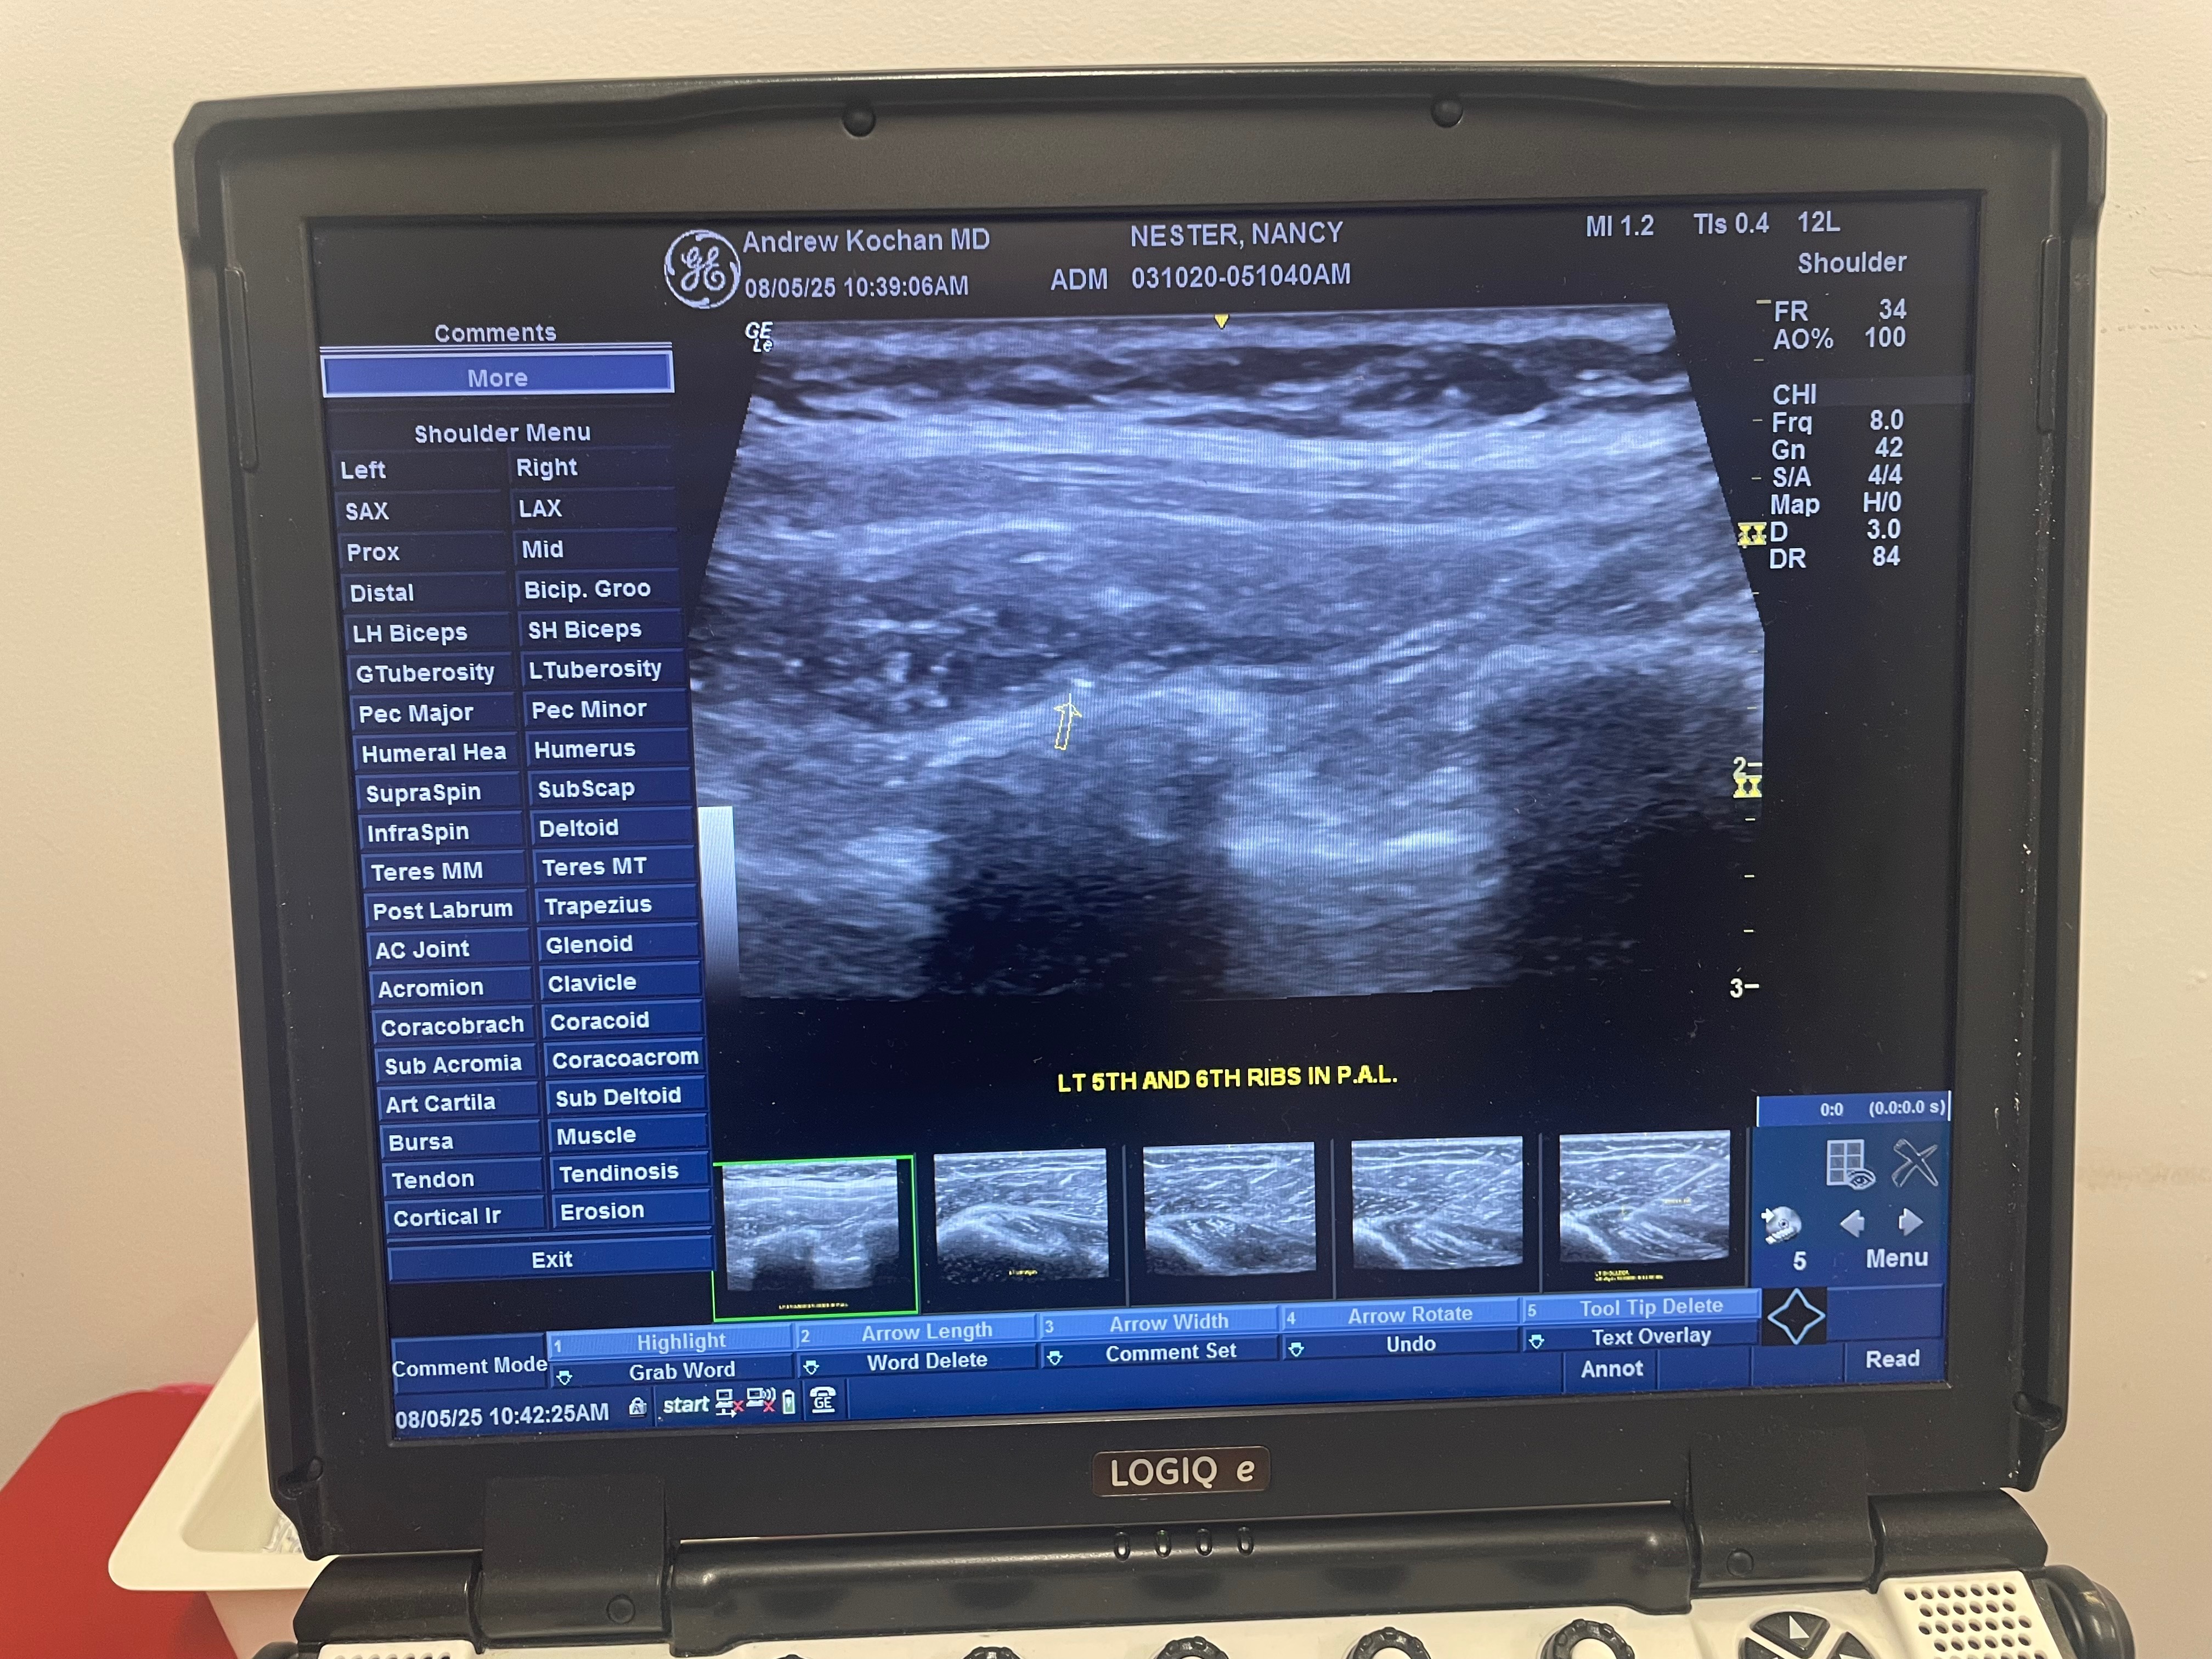

On the 4th of July she was lifted off the ground by her rib cage and tilted and continuously squeezed. Her two ribs 5&6 were popped out and now she is in constant agonizing pain!

These treatments consist of chiropractic rib adjustments and Prolo Therapy injections that only an MD can perform. The treatment will last anywhere from 16-24 weeks weeks!